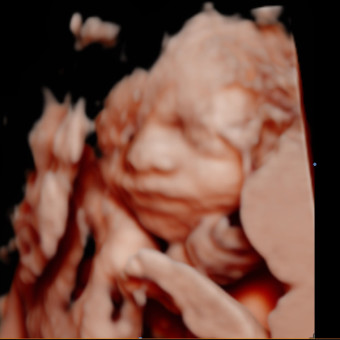

Roberta's Baby Registry

Roberta Chacon Pace & Conner Pace

December 13, 2025

Thank you for celebrating the arrival of our baby Thomas! We’re so grateful for your love and support, and we feel so blessed to have family and friends like you to share in this special time. Any contribution means the world to us. 🩵👶🏻